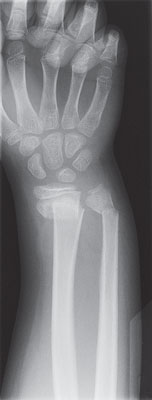

Bone X-ray

A bone X-ray is a way to take pictures of bones. It may also be called bone radiography. In this test, a low dose of radiation is passed through the body, producing digital images of the bones or images on a piece of film.

| X-ray of a broken wrist |